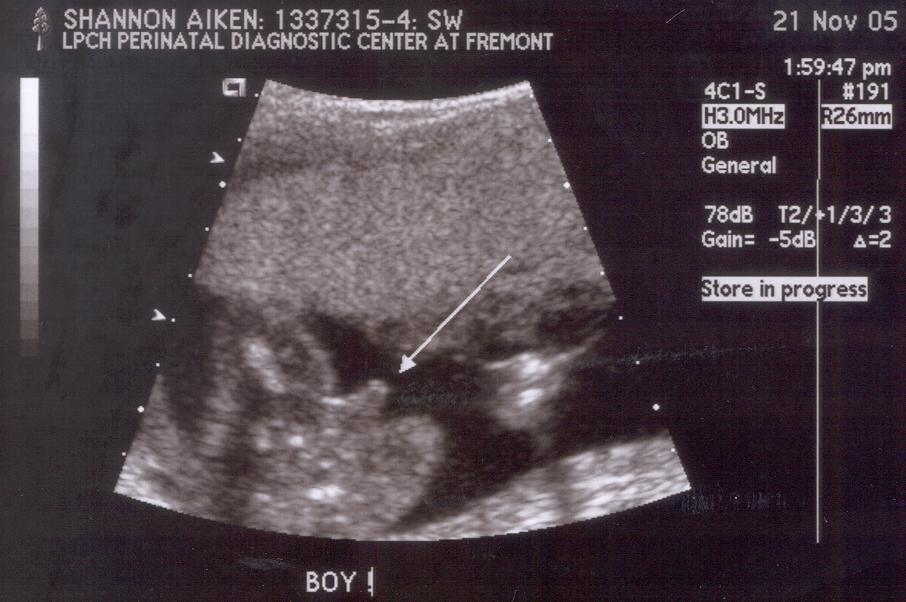

20 weeks: